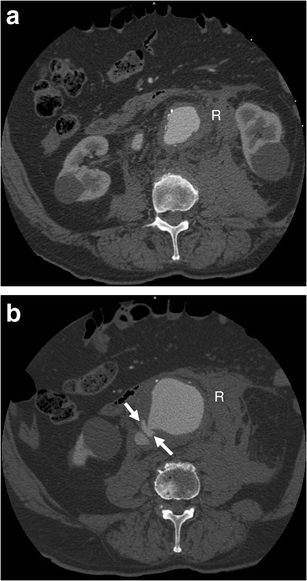

Aortocaval fistula. a Axial arterial phase enhanced CT shows simultaneous enhancement of the AAA and IVC in an 83-year-old man with AAA rupture and retroperitoneal haematoma (R). b Axial enhanced CT of the same patient at a lower level demonstrates active contrast extravasation (white arrows) from the aortic aneurysm to the IVC with loss of normal fat planes between the structures. Retroperitoneal haematoma (R) can also be seen